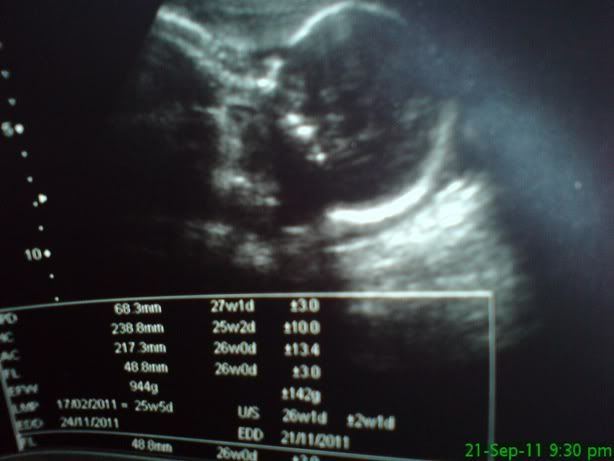

感觉Dr.Voon会给scan照多一点,我后期产检一张scan也没有拿到 |